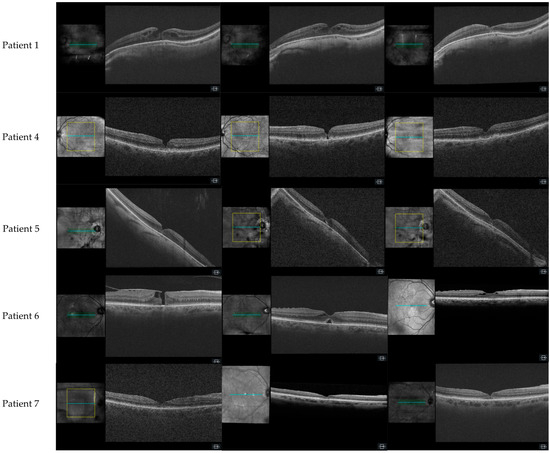

3.1.1. Patient 1, Left Eye

3.1.4. Patient 4, Left Eye

3.1.5. Patient 5, Right Eye

3.1.6. Patient 6, Right Eye

3.1.7. Patient 7, Right Eye

| 1 | No | No | Yes | Yes | Yes | Yes | FTMH | 30 | 4 | - | Yes | Yes | No | No |

| 5 | Complete | - | No | Yes | Yes | No | LMH | 180 | 5 | - | Yes | Yes | Yes | Yes |

| 6 | Partial | Complete | No | Yes | Yes | Yes | FTMH | 230 | 14 | - | Yes | Yes | Yes | Yes |

| 7 | Complete | - | No | Yes | Yes | No | LMH | 210 | 12 | 2 | No | Yes | Yes | No |